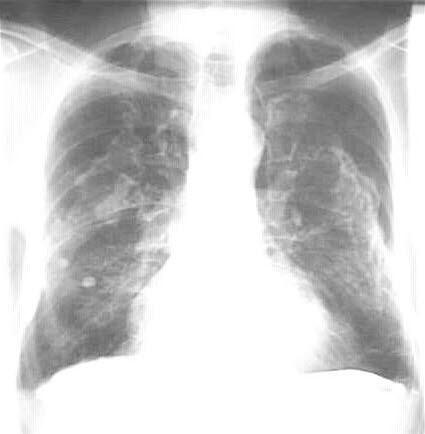

Asbestose er en sykdom som skyldes innånding av asbeststøv. Over tid fører dette til at lungevev omdannes til arrvev (lungefibrose). Typisk for denne formen for lungefibrose er at den utvikler seg i mellomrommene mellom de ulike delene av lungevevet (interstitielt).

Hos mange er dette en mild og lite plagsom sykdom. Tiden det tar fra du utsettes (eksponeres) for asbest og til sykdommen oppdages, er vanligvis 15-30 år. Andre asbest-relaterte lungesykdommer er lungekreft, lungehinnekreft (mesoteliom) og pleurale plakk. Inhalasjon av asbestfibre ble første gang knyttet til utvikling av lungesykdom i 1890.